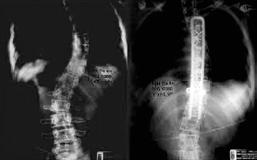

El consenso mundial de expertos en cirugía de columna reconoce que la etapa moderna de la cirugía se inicia con el uso de los nuevos elementos para estabilizar la estructura vertebral. Como mencioné anteriormente, en la Clínica de Columna iniciamos aplicando técnicas que estaban probadas para la escoliosis. Utilizamos halos cefálicos para tracción cervical, lo que nos permite lograr la reducción temprana de luxaciones cervicales; también empleamos

halos chalecos y la tenaza de Gardner Wells, que no habían sido aplicados en México para el tratamiento de trauma, como instrumentos de reducción.

Para la estabilización quirúrgica, inicialmente utilizamos las barras de “Harrington” de distracción y compresión, posteriormente utilizamos el sistema de “Luque” que modificamos para obtener mejor estabilidad en la reducción de fracturas, con muy buenos resultados. Con el desarrollo exitoso del sistema de “Cotrel-Dubousset”, mediante tornillos transpediculares, técnica que nos mostró y dirigió en su aplicación el Dr. Harry L. Shufflebarger, del Miami Children´s Hospital, iniciamos la exploración de otros sistemas similares como el TSRH del grupo médico del Texas Scottish Rite Hospital.

Rectángulo modelado con dispositivo de cierre “Codo de Dufoo”

Una vez que iniciamos el uso de la técnica del Dr. Eduardo Luque R. para la estabilización vertebral, encontramos que la técnica presentaba un problema. Al ajustar los alambres sublaminares a las barras laterales, se desplazaban hacia la línea media, perdiendo estabilidad y facilitando la rotación. Además, las barras rectas forzaban las curvaturas vertebrales naturales, originando “espaldas planas”. Esto se solucionó al diseñar una barra en forma de rectángulo, cerrando los extremos firmemente con un codo, lo que nos permitía modelarla sobre las curvaturas de la región vertebral, mejorando la estabilidad sin deformar el perfil del raquis. Esta técnica sigue siendo utilizada en la actualidad, para algunos pacientes. Resultados publicados.

Sistema “SD” de instrumentación vertebral

Durante el periodo de estabilización vertebral con el uso de tornillos transpediculares, se presentaron dificultades con los tornillos de base fija, lo que obligaba a la recolocación frecuente del tornillo por no estar alineado con la barra. Con la aparición de los tornillos con base móvil, este problema se volvió menos frecuente. Sin embargo, consideramos que “el raquis del paciente debe ajustarse al perfil del implante”. Este criterio fue discutido con diferentes asesores de los centros de investigación mencionados previamente.

Por ello, diseñamos un sistema de barras sujetas con tornillos transpediculares, permitiendo que el ensamble sea ajustable al ángulo de colocación del tornillo transpedicular, a la curvatura vertebral, a la distancia interpedicular y a la distancia entre segmentos vertebrales. Con esta flexibilidad de orientación en los ensambles, logramos que el sistema de estabilización “SD” se adapte a la anatomía vertebral del paciente sin modificar la resistencia de la instrumentación ni forzar los ensambles. Resultados publicados.